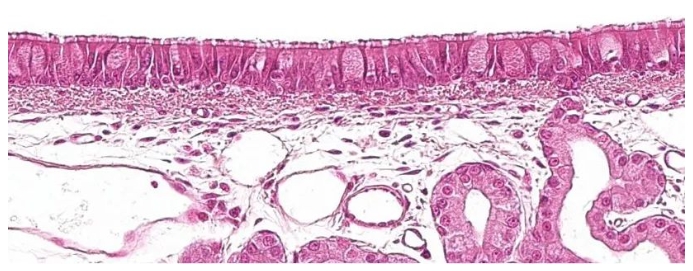

呼吸系統(tǒng)的第一部分,傳導區(qū)或呼吸區(qū),從鼻腔到細支氣管的最后一個分支,還包括與鼻腔相連的鼻竇和副鼻竇、鼻咽部和喉部。 所有這些管狀結構都內(nèi)襯有帶有杯狀細胞的纖毛假復層上皮(圖1),這是呼吸粘膜的主要防御系統(tǒng)之一,粘液纖毛系統(tǒng)。 該系統(tǒng)由呼吸道上皮細胞的纖毛,以及來自杯狀細胞的分泌物和位于呼吸道粘膜下方的漿液腺組成。它們的主要功能是清除通過吸入空氣進入的顆粒。腺體在纖毛之間分泌一種透明、低粘度、富含蛋白質(zhì)的液體,形成一種促進纖毛向上運動的介質(zhì)。 杯狀細胞分泌的粘液沉積在纖毛上,允許吸入的顆粒粘附。纖毛的向上運動將粘液推向上呼吸道;然后,粘液可以被吞下并進入消化道,在那里被消化,或通過口腔和/或鼻腔排出。導致纖毛丟失的肺炎支原體,或導致上皮細胞破壞的豬流感或呼吸道冠狀病毒等病原體,通過破壞這種防御系統(tǒng)來發(fā)揮致病作用。 與呼吸道粘膜相關的是支氣管相關淋巴組織(BALT),其中淋巴細胞與來自外部病原體的抗原相互作用,引起特定的防御反應,從而避免了全身免疫反應。其特征是通過IgA的體液免疫反應的介導,IgA通過主動運輸?shù)姆绞竭x擇性地分泌在粘膜表面。

圖1:帶有杯狀細胞的纖毛假復層上皮,是呼吸系統(tǒng)的特征